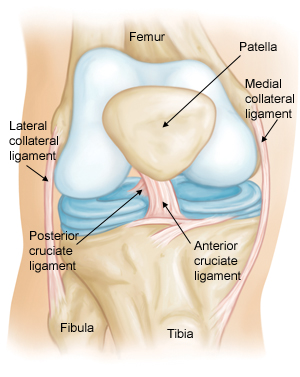

Anterior Cruciate Ligament

Knee Scanning Protocol (click image to view)

Meniscal Tears

Bulging meniscus with horizontal tear